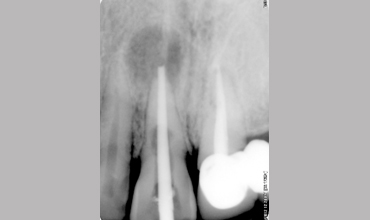

Management Of Internal Root Resorption In Maxillary Central Incisor Pre-operative Radiograph Removal Of Granulation Tissue With Ultra

Management Of Internal Root Resorption In Maxillary Central Incisor